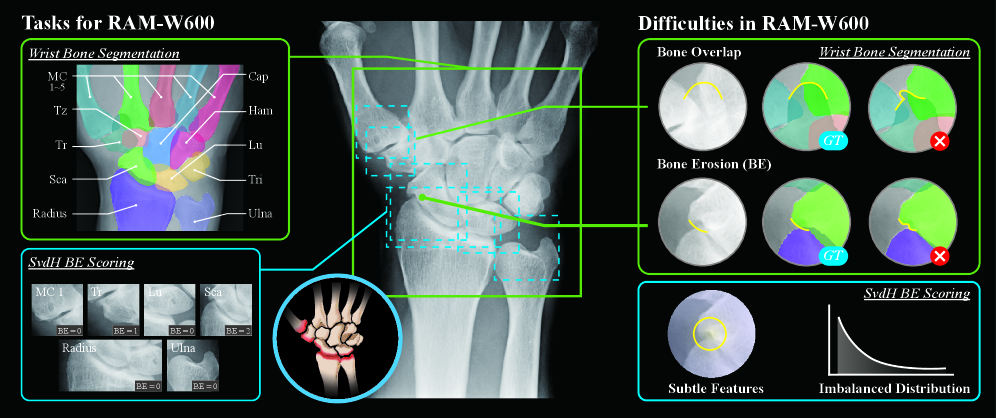

Refer to caption

Figure 1: Overview of the RAM-W600 dataset, designed for wrist bone segmentation and SvdH BE scoring tasks. (MC 1 to 5: Metacarpal 1 to 5; Tz: Trapezoid; Tr: Trapezium; Sca: Scaphoid; Radius: DistalRadius; Cap: Capitate; Ham: Hamate; Lu: Lunate; Tri: Pisiform &\& Triquetrum; Ulna: DistalUlna)

However, the annotation process of a large-scale dataset is highly challenging and labor-intensive due to the anatomical complexity of the wrist and different pathological changes in the wrist bones. As shown in Fig. 1, (i) Obscured edges due to overlapping structures. The wrist, a structurally complex joint system, features tightly interlocked carpal bones bhat2011radiographic . This configuration frequently leads to overlapping phenomena in conventional radiography (CR), which significantly complicates the identification of each bone’s outer edges. (ii) Morphological alterations resulting from pathological conditions. Due to the progression of RA and other pathological changes, BE, JSN, and osteophyte formation can affect certain bones or joints to varying degrees, often leading to substantial alterations in bone morphology taouli2004rheumatoid ; ezzati2022radiographic ; hoving2004comparison . Moreover, these factors may interact in diverse and combinatorial ways, further complicating the consistency and accuracy of annotations.